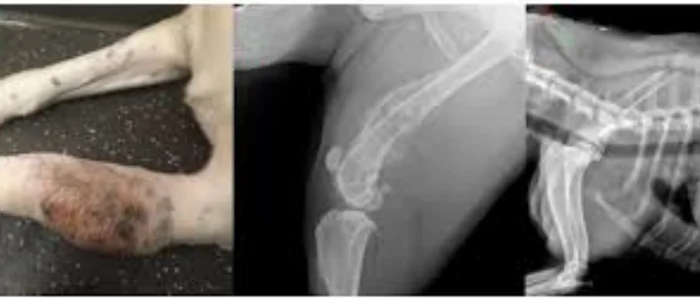

Kemik kanseri (osteosarkom) özellikle büyük ırk köpeklerde sık görülür ve nedensiz topallığa neden olur.

Osteosarkom: Kemik kanseri